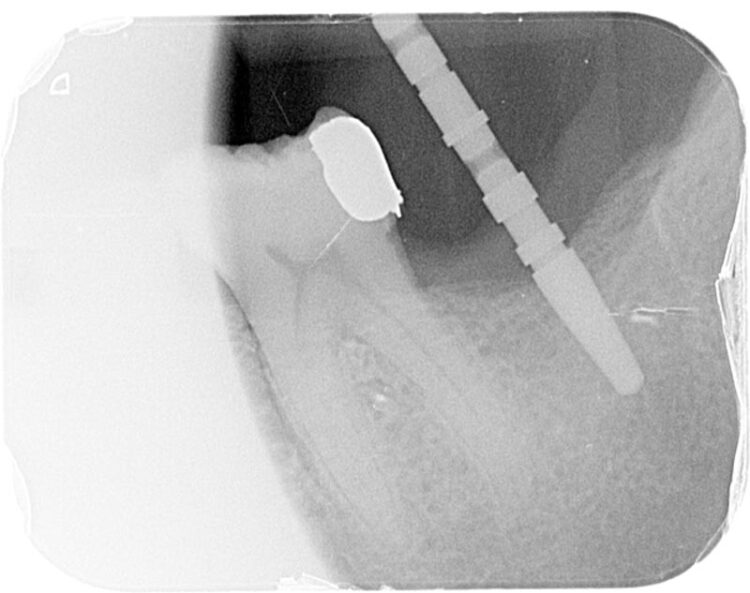

Following three months of healing, a CBCT scan was taken to assess bone dimensions and proximity of nearby anatomical landmarks, namely the inferior dental nerve and the lingual undercut of the mandible.

3-D radiographic examination showed sufficient bone available for the placement of a 5.8mm x 9mm BioHorizons Camlog tapered tissue level implant. Surgical placement of this implant involved a two-sided flap and there was no need for hard or soft tissue augmentation. The implant was placed with excellent primary stability and therefore a single-staged approach was followed with a healing abutment being placed at implant placement.